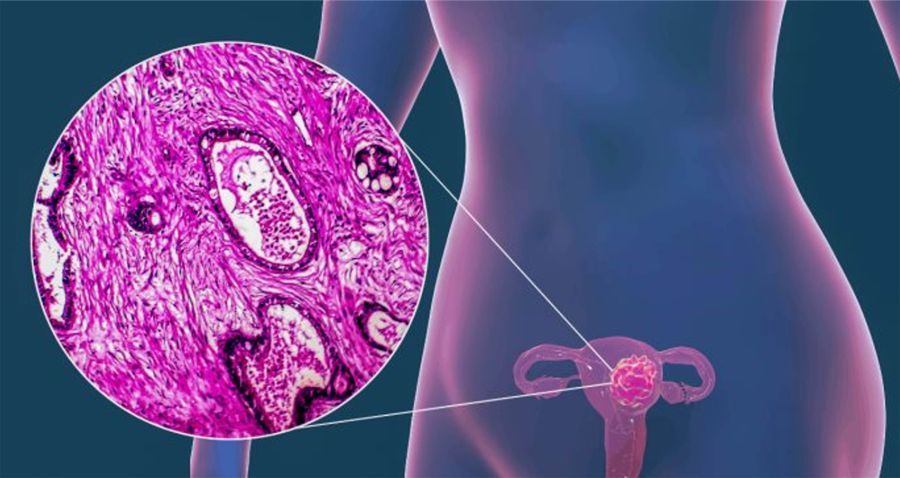

El virus de papiloma humano (VPH) y el cáncer cervicouterino son padecimientos de alto impacto a nivel global. De acuerdo con organismos internacionales como la Organización Mundial de la Salud (OMS), más de 80 por ciento de la población con vida sexual activa podría adquirir el virus, señala César Torres Cruz, del Centro de Investigaciones y Estudios de Género de la UNAM.

Solorza Luna recuerda que este padecimiento es causado por el virus de papiloma humano (VPH) que se propaga a través del contacto sexual con una persona infectada; y cuando la mujer tiene múltiples parejas sexuales se expone también a diversas infecciones.

Existen 200 tipos virales y las vacunas abarcan nueve u 11, que son de los más oncogénicos (causantes de cáncer); sin embargo, “he visto evolucionar a cáncer a algunos que son considerados de bajo riesgo. Servirán probablemente, pero lo más importante es usar preservativo durante las relaciones sexuales, principalmente cuando la pareja no es estable; las mujeres no deben permitir relaciones sin condón”, señala.

Comenta que el VPH puede tener una relación causal para derivar en casos de cáncer cervicouterino, aunque no es la única condición para desarrollarlo. Encontró que “centrarse sólo en ese cáncer contribuye a alejar la atención del virus y de la salud sexual de las mujeres”.

Hay que preguntarse también qué sucede con otros estragos que derivan del virus, como el cáncer anal en varones con prácticas homoeróticas; y se requiere abrir el panorama para comprender lo que ocurre con otros padecimientos, como el cáncer bucal o faríngeo.